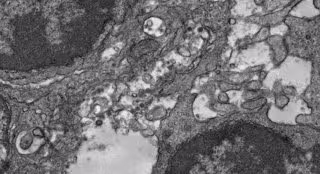

Imagen de microscopía electrónica del tejido de un ganglio linfático de un ratón que fue inmunizado con esta vacuna experimental contra la COVID-19.

Por último, los investigadores examinaron el proceso biológico de inducción de la inmunidad, mostrando con microscopía electrónica en los ganglios linfáticos de los ratones inmunizados cómo sus partículas de la vacuna experimental se enganchan a las células dendríticas foliculares (células inmunitarias que recogen y presentan las partículas virales para ayudar a iniciar una respuesta inmunitaria robusta), así como a las células B productoras de anticuerpos.

Compararon este acoplamiento con el de un diseño de proteína de espiga suelta, y los resultados sugirieron, según varias medidas, que la nueva vacuna candidata basada en nanopartículas es muy superior en su capacidad de estimular estos elementos inmunitarios. Por ejemplo, las partículas de la vacuna basada en nanopartículas se desplegaron cuatro veces más en las células dendríticas foliculares, y estimularon respuestas de células B mucho más largas y grandes, conocidas como reacciones del centro germinal.